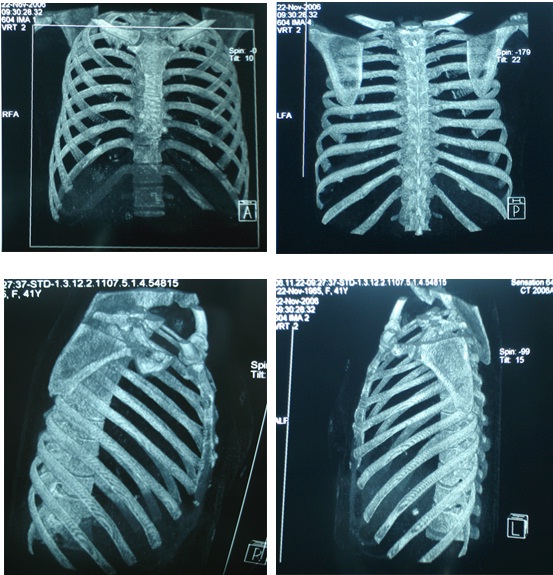

Năm 2006 bệnh nhân đến BV Bạch Mai khám định kỳ được làm các xét nghiệm siêu âm ổ bụng, chụp CT ngực 64 dãy, CT ổ bụng... nhưng không phát hiện thấy bất thường. Chất chỉ điểm khối u trong giới hạn bình thường.

BN được chỉ định làm xạ hình xương toàn thân để kiểm tra tổng thể toàn bộ hệ thống xương, phát hiện ổ di căn xương sườn số 4 trái.

Bệnh nhân được tiếp tục điều trị phác đồ FOLFIRI 6 chu kỳ, thuốc chống huỷ xương. Hiện tại, khám lại BN sức khoẻ tốt, bệnh ổn định và trở về công việc hàng ngày bình thường.

Bàn luận: Trong điều trị ung thư việc xác định đúng giai đoạn bệnh có ý nghĩa quyết định phương pháp điều trị, từ đó mang lại hiệu quả điều trị tốt nhất cho người bệnh. Nếu chỉ dùng các phương pháp chẩn đoán thông thường rất dễ bỏ sót tổn thương qua đó đánh giá không đúng giai đoạn bệnh. Sự ra đời của các máy SPECT, PET, SPECT/CT, PET/CT ghi hình ở mức độ tế bào, mức độ phân tử, theo nguyên tắc chuyển hoá khi chưa có sự thay đổi về giải phẫu thực sự, là bước tiến quan trọng trong việc phân loại đúng, sớm giai đoạn bệnh cũng như việc điều trị ung thư. ở BN này, bằng các kỹ thuật chẩn đoán thông thường (ngay cả với CT 64 dãy đầu dò) đều cho kết quả hoàn toàn bình thường, nhưng khi dùng kỹ thuật xạ hình bằng máy SPECT đã phát hiện ổ di căn xương trên xạ hình xương thì thái độ điều trị đã hoàn toàn thay đổi. BN được tiếp tục điều trị hoá chất và chống huỷ xương, hiện tại bệnh nhân khoẻ mạnh, bệnh ổn định.